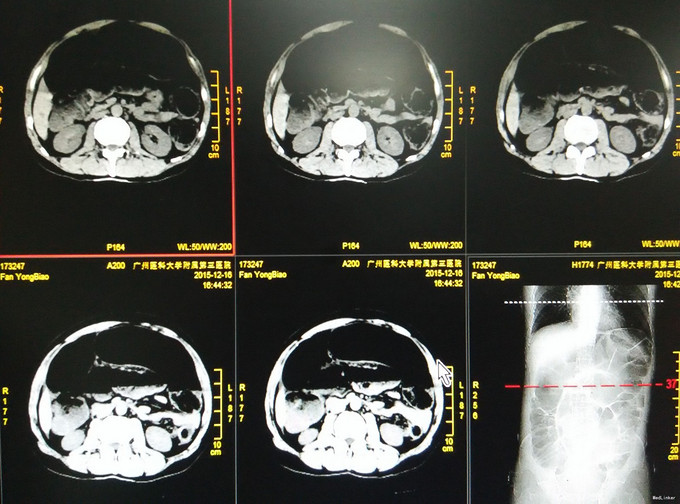

外科情况:腹胀,未见腹壁静脉曲张,未见胃肠型及蠕动波,腹肌软,全腹未扪及包块,脐上压痛,无反跳痛,肝脾肋下未及,双上、中输尿管点、肋脊点、肋腰点无压痛,双肝肾区无叩痛,移动性浊音阴性,肠鸣音0次/分。 辅查:我院急诊腹平片提示不完全性低位肠梗阻征象。 CT:1、拟乙状结肠近段、远段肠扭转并结肠低位肠梗阻,乙状结肠中段、降结肠、结肠脾曲、肝曲、升结肠及部分小肠明显积液、扩张;腹腔少量积液;2、肝脏多发小囊肿;3、胆囊、胆囊颈多发结石并慢性胆囊炎,肝内、外胆轻度扩张。

诊断:腹痛查因:肠梗阻? 治疗:患者机械性肠梗阻,CT提示乙状结肠扭转,有急诊手术指征,完善术前准备,拟急诊行剖腹探查、乙状结肠扭转复位、备乙状结肠切除术。 术中探查:腹腔少量淡黄色腹水,吸尽量约50ml,乙状结肠冗长,距腹膜反折以上约25-55cm乙状结肠及其系膜顺时针扭转约540度,扭转肠管呈闭攀性梗阻改变,扩张充血明显,系膜血管搏动良好,肠壁血运正常,未见坏死、穿孔;余升结肠、横结肠、降结肠及直肠未见明显占位病变,肝胆、脾脏未及明显异常,腹主动脉旁无肿大淋巴结。 考虑乙状结肠冗长并肠扭转诊断明确,决定行乙状结肠扭转复位+乙状结肠切除术